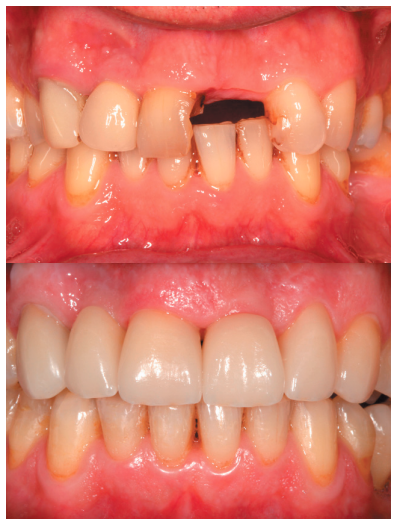

La fluorosis dental es una condición irreversible originada durante el desarrollo dental que genera pigmentaciones intrínsecas, alteraciones en el esmalte manifestadas a manera de manchas blancas, amarillas o marrones, que perjudican la estética y repercuten en el desenvolvimiento social. El presente reporte de caso clínico describe la combinación de los procedimientos de microabrasión y blanqueamiento dental, como alternativas en la eliminación de pigmentaciones dentales. Después del diagnóstico de la patología, verificación de ausencia de lesiones pulpares y caries, una explicación minuciosa a la paciente y obtención del consentimiento informado, se realizó limpieza de las superficies dentales y, bajo aislamiento absoluto, se procedió a realizar la técnica de microabrasión mediante ácido clorhídrico al 6,6% siguiendo las instrucciones del fabricante. Concluido el procedimiento y, observando que era posible mejorar aún más la estética, se decidió ejecutar el procedimiento de blanqueamiento dental, a base de peróxido de hidrógeno al 40% en el consultorio, seguido por peróxido de carbamida al 10% aplicado en el domicilio. Al finalizar el tratamiento se observó uniformidad en el color dental, conjugados con una evidente mejora en la calidad de vida y relación social de la paciente.

La combinación de procedimientos, como el reportado en este caso, constituye una excelente alternativa de tratamiento para eliminar pigmentaciones fluoróticas moderadas.